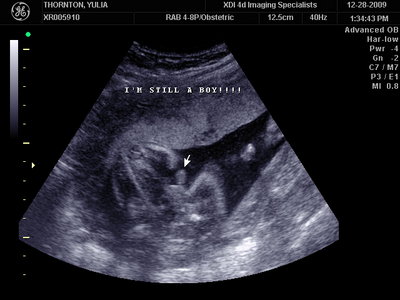

Ну ладно, тогда и я нашего писюна покажу  Надеюсь, Джеффри на меня не обидится Вот это в 23 недели: (там оборудование переключалось из режима 3Д в обычный 2Д)

| Вложения: |

MY BABY SONO!_2_15.JPG [ 112.35 КБ | Просмотров: 1364 ]

Sweetheart75 писал(а): Ну ладно, тогда и я нашего писюна покажу  Надеюсь, Джеффри на меня не обидится Вот это в 23 недели: (там оборудование переключалось из режима 3Д в обычный 2Д) Oоо, такое достоинство невозможно не заметить  А в 30 недель так вообще!